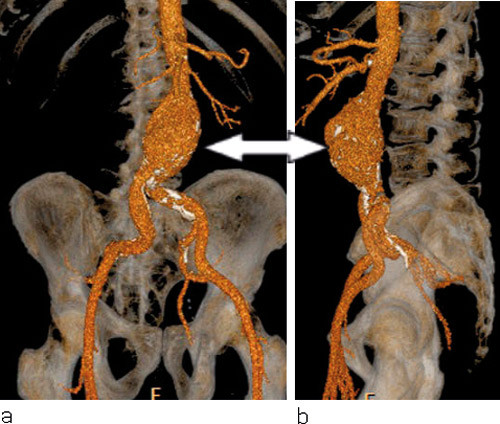

«Aneurisme» kommer fra det greske verbet «aneurynein», som betyr «å utvide». Et abdominalt aortaaneurisme er en utposning på hovedpulsåren som gir minst 50 % økt diameter (1). En mer praktisk definisjon som brukes ofte er aortadiameter > 30 mm (2). Figur 1 er en fremstilling av kartreet i abdomen med aortaaneurisme. Ruptur av aneurismet gir blødning ut i omgivende vev og medfører en livstruende tilstand hos pasienten – ubehandlet er utgangen dødelig (fig 2). Det er beregnet at om lag 1–2 % av dødsfallene i den vestlige verden skyldes rumpert aortaaneurisme (3). Tilstanden kan utvikle seg i hele aorta, men er hyppigst forekommende i infrarenale abdominalaorta. Data i denne artikkelen vil derfor vesentlig omhandle abdominalaorta med eller uten involvering av iliakalkar.

Ultralyd er en rask, ufarlig og billig undersøkelse som er velegnet til diagnostikk og kontroll av aortaaneurismer frem mot behandling, og den brukes ved screeningprogrammer. Den kan som hovedregel ikke avgjøre om det foreligger ruptur. Det kan raskt avklares med høy treffsikkerhet ved CT-angiografi. Slik kontrastforsterket spiral-CT er etter hvert blitt hovedmetoden ved diagnostikk og planlegging av operasjon for aortaaneurismer og anses som nødvendig preoperativ undersøkelse ved endovaskulær behandling. Med ulike dataprogrammer kan tredimensjonale (3D) rekonstruksjoner og «utbrettinger» lages for preoperativ planlegging og måltaking til endovaskulære proteser (stentgraft).